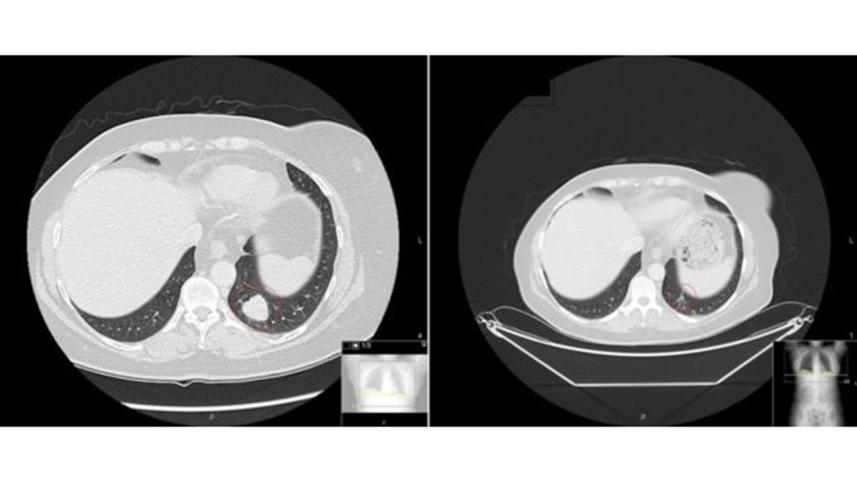

Melanoma before and after therapy. Photo: BBC/ Royal Marsden

Vicky Brown, 61 and from Cardiff, was diagnosed with malignant melanoma that had spread to her lungs and breast in April 2013.

She started the combination therapy later that year.

"It worked within a month. There were lumps I could actually feel and they disappeared quite quickly," she told the BBC.

She did face severe side effects including an upset liver and inflamed bowels and a year later the cancer returned.

She is now on her second course of combination immunotherapy, which again seems to have shrunk the tumours.